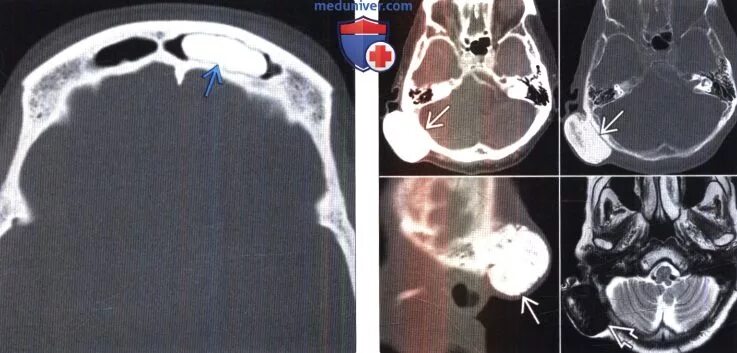

Остеома мрт